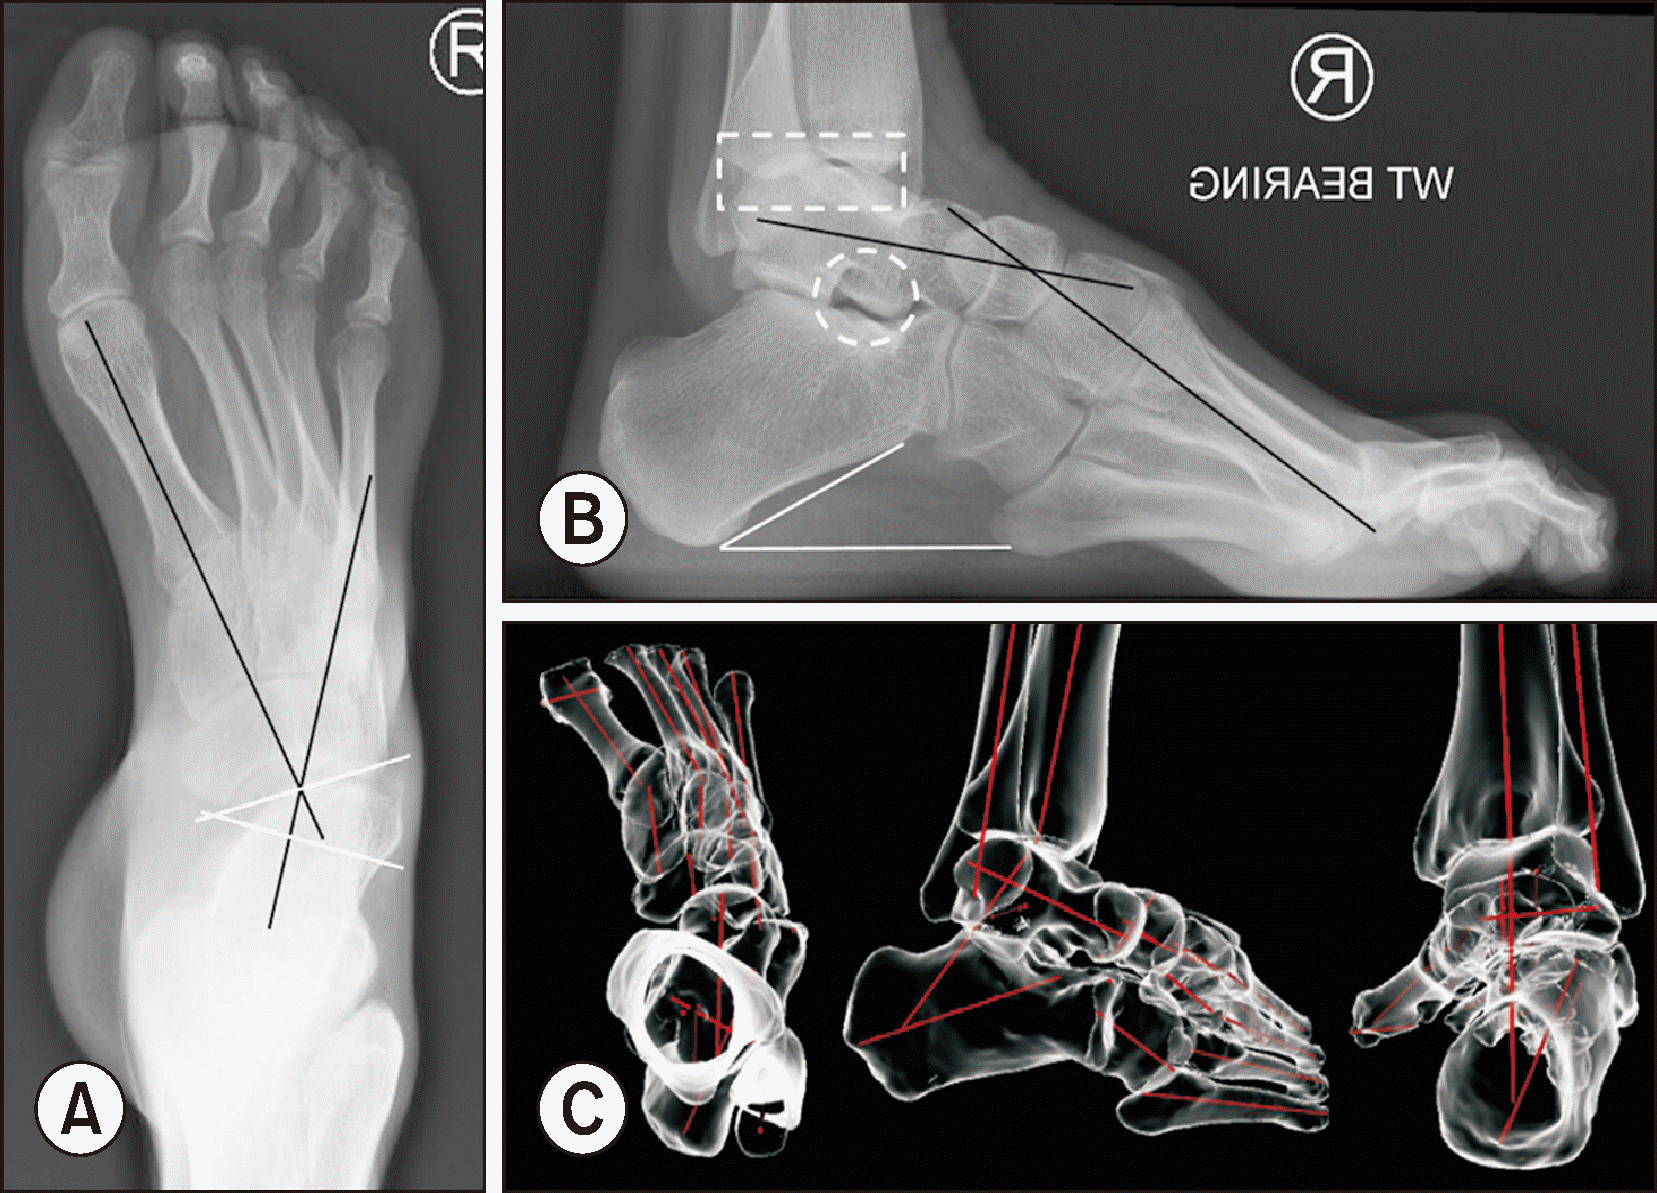

방사선 촬영은 CMT 요내반족의 진단에 있어 가장 표준이 되는 검사로, 체중부하 족부 전후면, 족부 측면, 족관절의 전후면 혹은 모티스 영상(mortise view) 및 후족부 정렬 촬영(hindfoot alignment view) 등이 진단을 위해 권고된다.3,10) 족부 전후면 사진에서 전족부 또는 중족부의 내전 정도를 평가하기 위하여 거골의 종축과 제 1중족골의 종축 사이의 각도를 재는 축상 Meary angle과 거주상 관절 피복각(talonavicular coverage angle)을 측정할 수 있다. 족부 측면 사진에서는 요족의 정도를 평가하기 위하여 시상 Meary angle과 종골 경사각을 측정할 수 있다. 종종 CMT 환자들의 종골 경사각이 역설적으로 정상 범위를 보이는 경우가 있는데 이는 중족부의 심한 회외 변형으로 인해 나타나며, 이로 인해 종골의 배측 굴곡이 상쇄되기 때문이다.14) 후족부 정렬 사진에서는 후족부 내반 정도를 평가하기 위하여 후족부 모멘트 암(hindfoot moment arm)과 후족부 정렬각(hindfoot alignment angle)을 측정한다(Table 1).8,10) 족관절의 전후방 또는 모티스 사진에서는 거골의 내반 경사를 측정하고 족관절의 관절염 병변을 확인할 수 있다.

이 외에도 CMT 족부 변형에서 관찰할 수 있는 특징적인 영상의학적 소견들이 있다. CMT 족부에서 후족부 내반과 전족부 내전이 동반되면서 발생되는 후족부 및 발목의 외회전 변형으로 족근동(sinus tarsi)의 ‘see-through sign’과 ‘double talar dome sign’이 관찰될 수 있다.10) 중족골의 겹침(metatarsal stacking) 소견은 중족부의 회외 및 내번 변형으로 발생하는 영상 소견이다. 또한 후족부 내반, 중족부의 회외 변형으로 보행 시 제 5중족골에 반복적인 압력이 가해지는 경우가 많아 제 5중족골의 피로 골절이 드물지 않게 관찰되기도 한다.

컴퓨터 단층촬영(computed tomography, CT)이나 자기공명영상(magnetic resonance imaging)은 술자가 필요한 경우에 선택적으로 시행한다. 특히 복잡한 변형을 보이는 CMT 족부 변형은 기존의 기립 단순 방사선 영상과 2차원 CT 영상으로 정확한 분석이 어려운 한계가 있어 관찰자간 신뢰도가 떨어지는 경우가 흔한데, 최근에는 체중부하 CT (weight-bearing CT, WBCT)와 3차원 자동화 분석 소프트웨어(3D automated analysis software)를 이용해서 CMT 족부 변형의 보다 정확한 분석이 가능한 것으로 보고되었다(Fig. 3).11,15,16) WBCT 영상은 특히 후족부 정렬 및 발목 관절 상합성(congruity) 이상을 파악하는 데 유용한데, 자동화 분석 소프트웨어를 이용하면 각 뼈들의 중심축 사이의 각도를 자동으로 계측하기 때문에 검사의 정확도와 신뢰도가 높은 것으로 보고되었다.1,11,16) Song 등11)은 CMT 족부 변형 환자에서 수술 전후 족부의 시상면, 축상면, 관상면의 다면적 정렬 평가 시 3차원 자동화 분석 소프트웨어를 이용한 WBCT 분석의 유용성을 보고한 바 있다. 그러나 이러한 영상의학적 도구들은 수술적 치료 방향에 도움을 줄 수 있으나 절대적인 골교정을 위한 지표가 될 수 없으며, 최종적인 골교정술의 결정은 모든 연부조직 유리술이 시행된 이후에 결정되어야 한다.1)

Figure 3

Key radiographic measurements and signs for evaluation of CMT. (A) Anteroposterior radiograph with CMT shows the axial Meary angle (black angle), or the talonavicular coverage angle (white angle). (B) Lateral radiograph with CMT shows the sagittal Meary angle (black angle), or the calcaneal pitch angle (white angle). Double talar dome sign (dashed rectangle) and the sinus tarsi see-through sign (dashed circle) can be seen. (C) Segmental bone axes (red lines) analyzed by 3D automated analysis software in weight-bearing CT images. CMT: Charcot–Marie–Tooth, CT: computed tomography.